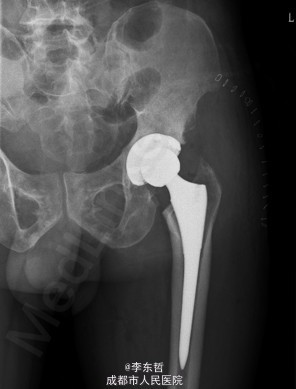

患者男,62岁,因“双髋疼痛4年,加重伴活动受限1年”入院。病员诉入院前4年无明显诱因出现双侧髋部疼痛,行走后疼痛加重,疼痛能忍受,双侧髋部无红肿,皮温不高,无畏寒、发热,休息后疼痛能自行缓解,无夜间疼痛,在当地医院行止痛药内服、理疗治疗,疼痛稍缓解。逐渐加重,1年前双侧髋部疼痛、跛行明显加重,左髋活动受限,行走困难,给予对症治疗症状无明显改善,遂到我科门诊就诊,X线片提示:双侧股骨头坏死,建议手术治疗,故于今日以“双侧侧股骨头坏死”收入我科进一步治疗。

查体:生命体征平稳,心肺腹未见异常;跛行,双左下肢较右下肢短缩1cm,左、右腹股沟中点深压痛,左、右髋叩击痛,左髋屈20°,伸0°,外展10°,内收10°,右髋屈60°,伸0°,外展20°,内收20°。双髋内、外旋活动受限,诱发疼痛,左侧重。 辅助检查:x线片示双侧股骨头坏死、塌陷变形,左侧明显,左髋半脱位。

初步诊断:1、左侧股骨头坏死伴内收肌挛缩(Ficat IV期);2、右侧股骨头坏死(Ficat IV期);3、右膝骨关节炎伴外翻畸形;入院后积极完善术前检查及准备,择期行手术治疗。